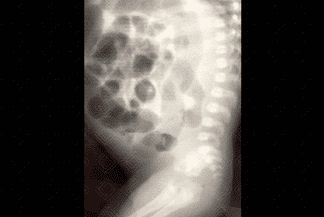

Texto alternativo para a imagem Figura 1. Crédito: Dra. Elazir Mota - Rio de Janeiro/RJ

Descrição das imagens: Clister opaco. Administra-se contraste baritado diluído por sonda retal, seguido da realização de radiografias em AP e perfil. Observa-se, já na fase de enchimento, a desproporção entre calibre do reto e sigmoide, sendo o reto bem menor (figuras 2 e 3). A radiografia simples do abdome em perfil auxilia na suspeição diagnóstica pela não visualização de gás na ampola retal (figura 1).

• Radiografia de abdome: A radiografia de abdome mostra distensão abdominal importante, notadamente do sigmoide. É comum a não visualização de gás no reto (mais evidente no estudo em perfil);